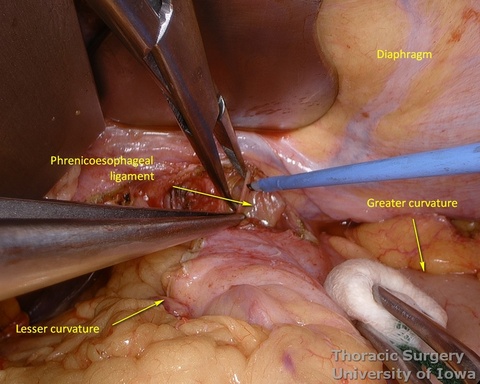

- Phrenoeosophagial ligament is formed by the transversalis fascia of abdomen and endothoracic fascia and is covered with the peritoneum. Thicker upper leaflet ascends obliquely and fuses with the adventitia of the esophagus above the diaphragm. The thinner lower leaflet runs caudally and attaches to the esophageal wall just cranial to the angle of His. The triangular space between the leaflets is filled with the perihiatal fat pad.

- The peritoneum is incised around the hiatus.

- The phrenoesophageal ligament is divided and the right crus dissected.

- Subhiatal fat ring is exposed after division of the lower leaflet of the phrenoesophageal ligament

- Procced with mobilization of the stomach. The course of the right gastroepiploic artery is determined.

- The gastrocolic ligament is incised in its avascular portion between the terminal branches of the right and left gastroepiploic vessels, and the lesser sac is entered.

- The gastrosplenic ligament is divided towards the hiatus, taking care to stay away from the gastroepiploic arcade.

- Fundus of the stomach is dissected free all the way to the esophageal hiatus dividing gastro-phenic ligament and remaining adhesions.

- The greater curvature of the stomach is then mobilized towards the pylorus, dividing the gastrocolic ligament no closer to than 1.5–2 cm to the right gastroepiploic vessels, while protecting the vessels with the fingers of the retracting hand. In morbidly obese patients the right gastroepiploic artery may not be visible or palpable. A Doppler probe is used then to identify its course and origin from the gastroduodenal artery.